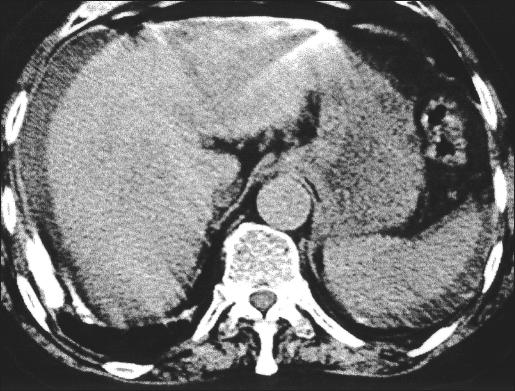

A 75-year-old woman affected by cirrhosis of the liver (Child class C) and chronic gastric ulcer presented with acute abdominal pain. The diagnosis of perforation was made with plain films of the abdomen and computed tomography. Diagnostic laparoscopy showed intense peritonitis due to a perforated ulcer of the anterior gastric wall, 2 cm proximal to the pylorus. Suture closure and placement of an omental patch were performed laparoscopically.

一名75岁患有肝硬化(Child C级)和慢性胃溃疡的女性出现急性腹痛。通过腹部平片和计算机断层扫描做出穿孔诊断。诊断性腹腔镜检查显示,幽门近端2厘米处的胃前壁溃疡穿孔导致严重腹膜炎。通过腹腔镜进行缝合关闭和网膜补片放置。